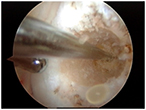

Arthroscopic photos from the surgery show removal of the os. The spinal needle is used to localize the os and demonstrate that it is loose. It is then removed arthroscopically with a burr. Care is taken to not disrupt the dorsal capsule.